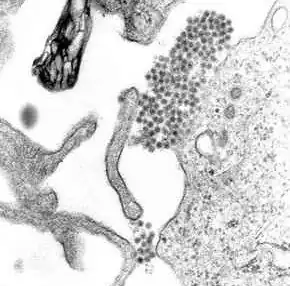

O vírus da dengue (DENV) é um vírus RNA da família Flaviviridae; gênero Flavivirus. Entre outros membros do mesmo gênero estão os vírus da febre amarela, da febre do Nilo Ocidental, da encefalite de São Luís, encefalite japonesa, da encefalite transmitida por carrapatos, da doença da floresta de Kyasanur e da febre hemorrágica de Omsk. A maioria deles são transmitidos por artrópodes (mosquitos ou carrapatos) e, portanto, também são conhecidos como arbovírus, termo derivado da expressão em língua inglesa "arthropod-borne viruses".[11]

O genoma (material genético) do vírus da dengue contém cerca de 11 000 bases de nucleotídeos, que codificam três tipos diferentes de moléculas de proteínas (C, prM e E) que formam a partícula viral e sete outros tipos de moléculas de proteína (NS1, NS2A, NS2B, NS3, NS4A, NS4B e NS5) que apenas são encontradas em células hospedeiras infectadas e são necessárias para a replicação do vírus.[23][24] Existem quatro cepas do vírus, que são chamadas de serotipos, as quais são referidas como DEN-1, DEN-2, DEN-3 e DEN-4.[13] As distinções entre os serotipos baseia-se na sua antigenicidade.[25]